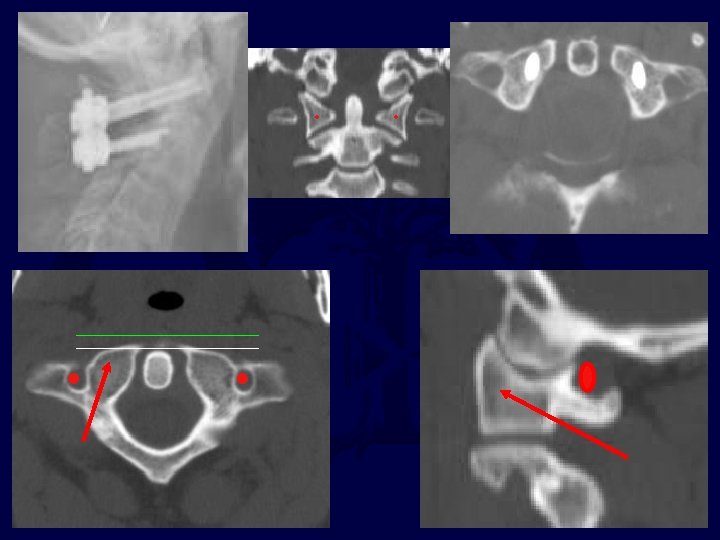

The course of the vertebral artery through C 1 and C 2 determines the possibility of placing screws for fixation of fractures and dislocations • C 1 lateral mass screws • C 1 -2 transarticular screws • C 2 pedicle/pars screws

pedicle Pars Trans-articular C 2 pars/pedicle